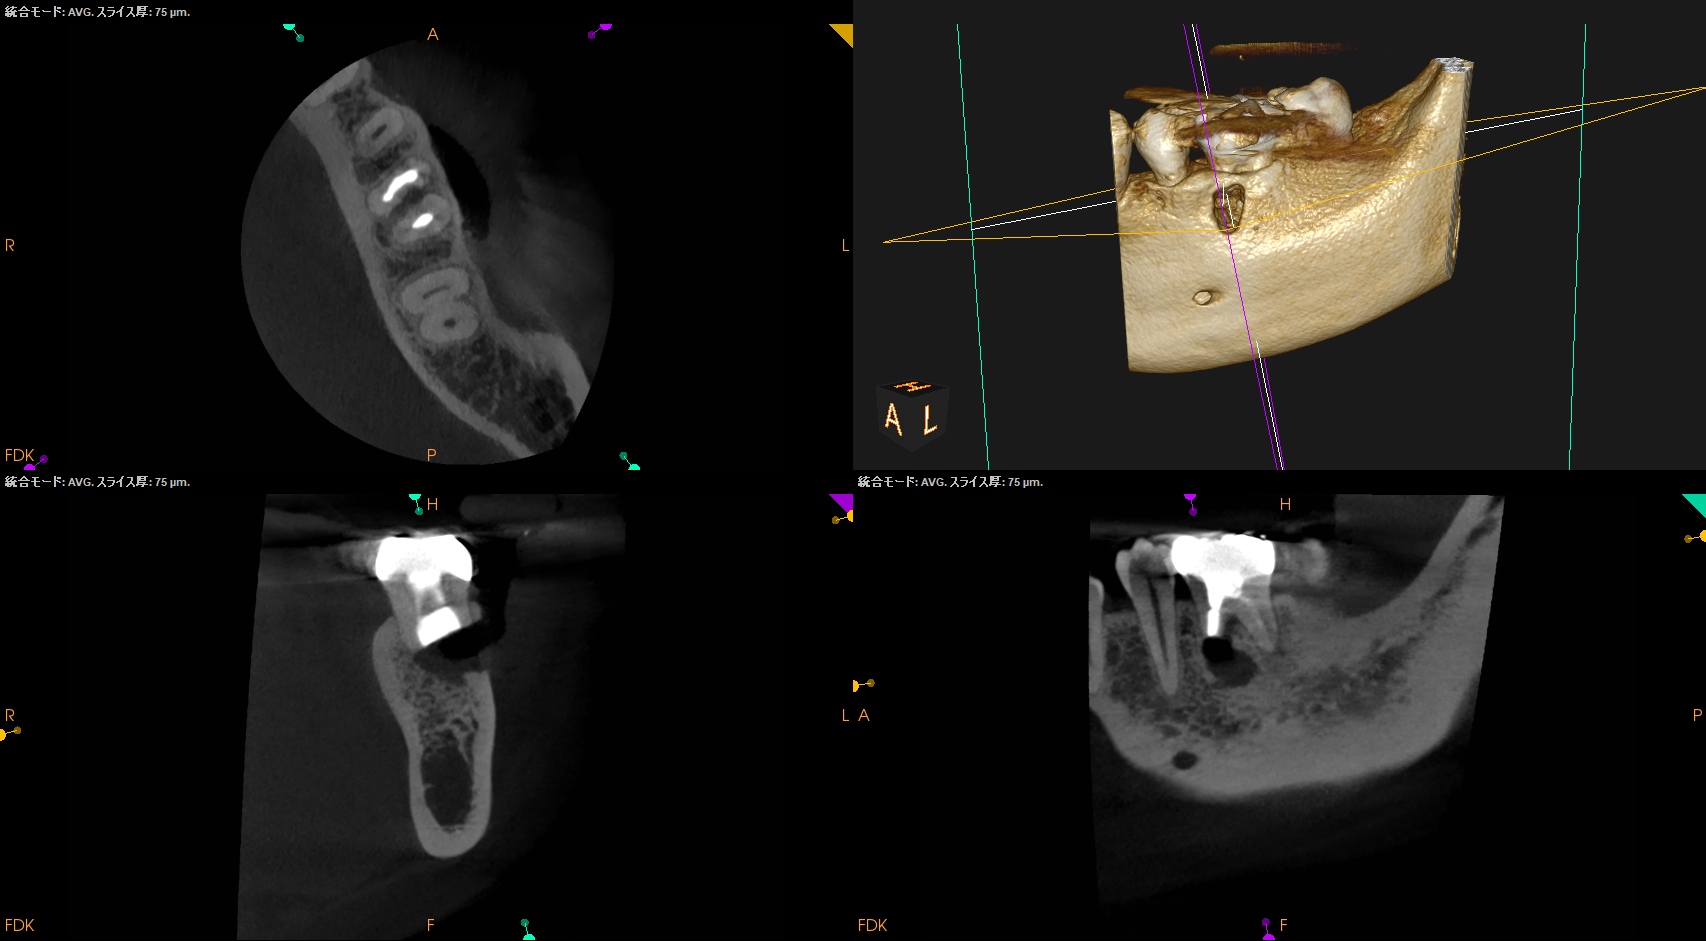

Pre-op Endo(2024.6.17)

#19 Cold N/A, Perc.(+), BT(+), Palp.(-), Perio Probe(WNL), Mobility(WNL)

臨床症状の原因は#19の近心根の根尖病変だろう。

再根管治療に見込みはないため、Apicoectomyなのだが

当該部位を2mm Osteotomyすると#19 MのApexが発見できそこを3mm切断するには頬舌径が6.2mm必要である。